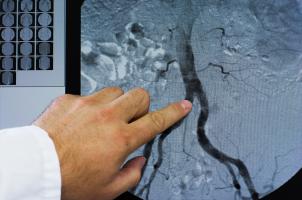

Actualité publiée le 08/11/2025ATHÉROSCLÉROSE : La technique d'imagerie qui surveille son évolution

ATHÉROSCLÉROSE : Des nanoplastiques à côté de la plaque

Actualité publiée le 31/03/2025ATHÉROSCLÉROSE : Même subclinique, c'est un prédicteur de mortalité

ATHÉROSCLÉROSE : Et si le cholestérol n'était pas le seul lipide impliqué ?

Actualité publiée le 21/11/2024ATHÉROSCLÉROSE : Des caractéristiques cliniques cancéreuses ?

ATHÉROSCLÉROSE : Réaliser les promesses des sphingolipides

ATHÉROSCLÉROSE : La plaque plus tardive mais plus nocive chez les femmes ménopausées

Actualité publiée le 16/06/2023ATHÉROSCLÉROSE : Prévenir l'obstruction des artères en boostant l’autophagie

ATHÉROSCLÉROSE : Mais comment stabiliser la plaque ?

Actualité publiée le 19/07/2022ATHÉROSCLÉROSE : Le laser qui vaporise la plaque

ATHÉROSCLÉROSE : La lipoprotéine A, le « meilleur » marqueur de risque ?

Actualité publiée le 08/04/2022ATHÉROSCLÉROSE : 40% des adultes en bonne santé ont des dépôts dans les artères

ATHÉROSCLÉROSE : Mission to MAARS